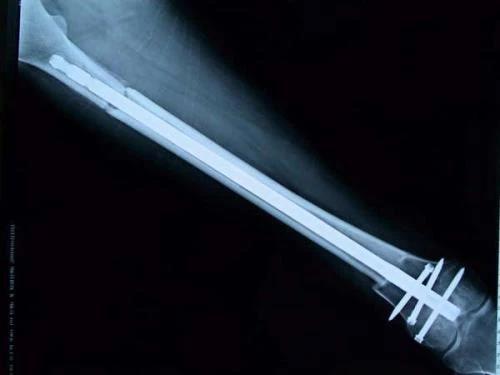

新輔助化療的目的是盡早殺滅遠處微小轉移灶,縮小腫瘤及周圍炎性水腫反應區,以利于后續的保肢手術;觀察腫瘤對化療的敏感性,為進一步指定個體化的術后化療方案奠定基礎。骨肉瘤新輔助化療下的保肢治療如下圖所示: